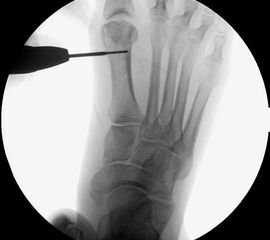

Präoperatives Röntgenbild Fuß d.p. mit eingezeichneten Winkeln. A) Intermetatarsalwinkel, B) Hallux valgus Winkel, C) Interphalangeal-Winkel.

Abbildung 2

• Operationsplanung anhand der Röntgenaufnahmen unter Beachtung wichtiger radiologischer Landmarks wie Intermetatarsalwinkel, Hallux valgus – Winkel, distaler Gelenkflächenwinkel (Distal Metatarsal Articular Angulation - DMAA), Metatarsaleindex und Sesambeinposition (Abb. 2).